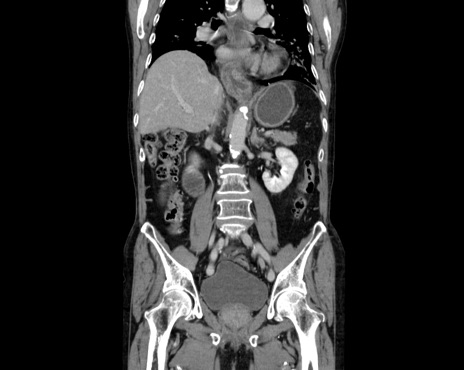

症例26(冠状断像)

【症例】80歳代男性

【主訴】嘔吐

【現病歴】昨晩2回嘔吐あり、今朝になっても嘔吐あり。来院。

【既往歴】胃潰瘍

【身体所見】意識清明、BT 37.6℃、BP 166/95mmHg、HR 100bpm、SpO2 97%、腹部:平坦・軟、腸蠕動音聴取良好、圧痛なし。

【データ】WBC 21900、CRP 1.4